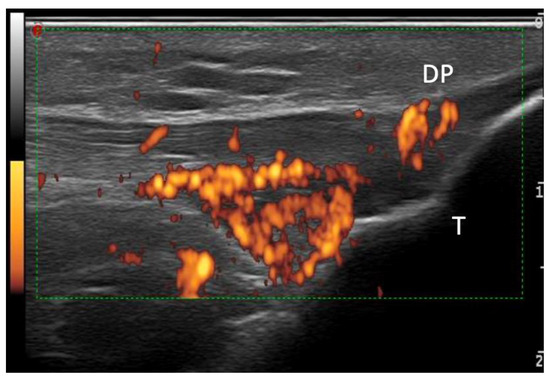

| DP (mean; SD) | 1.51 + 1.91 | 0.71 + 0.71 | 0.003 |

| Enthesis PD (mean; SD) | 0.41 + 0.43 | 0.15 + 0.12 | 0.212 |